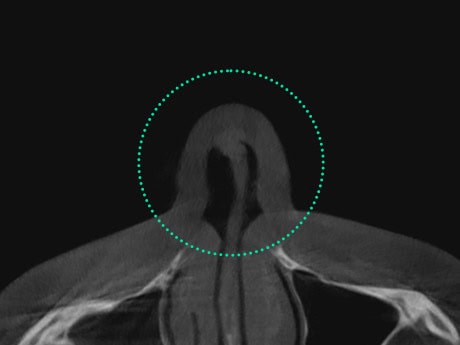

通过鼻内窥镜、3D-CT等对鼻内部结构与

组织状态进行精密检查后,制定手术方案。

通过3D-CT与内窥镜精密检查鼻内部结构与组织状态,

精准诊断隐藏问题,准确分析原因,

必妩整形医院通过整形外科与耳鼻喉科专家的协作诊疗,

结合3D-CT与内窥镜精准诊断,不仅对鼻塞、鼻炎、

鼻窦炎等鼻部问题带来的不适进行改善,同时塑造立体精致、

和谐美观的鼻部线条。